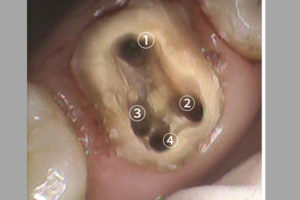

歯の神経の入口は奥歯の場合

通常3つしかない

と教科書では教えられています。

しかし、実際に私が全国からお越し下さる患者さんのお口の中を診せて頂き

根管治療(歯の神経治療)をしていく中では

歯の神経の入口は4つ、5つ目の神経

のある方がいらっしゃいます。

これは特に珍しいケースではなく、吉本歯科医院で来院される患者様の10人のうち5人の割合でいらっしゃいます。

4つ目の神経の入口を見つける時に

役に立つのが、マイクロスコープ(手術用顕微鏡)です。

肉眼では見えないものが

マイクロスコープ(手術用顕微鏡)を使うことによって

よく見えます。